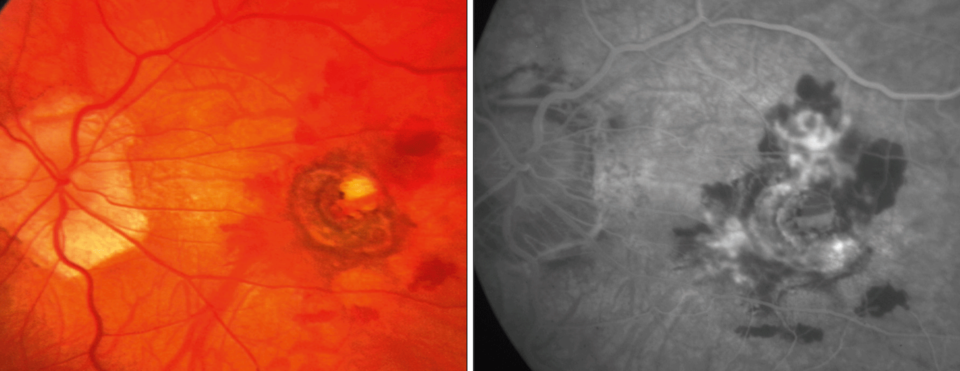

Abb. 2: Gefäßneubildung im Bereich der Makula bei einem Patienten mit krankhafter Kurzsichtigkeit – Augenhintergrund (links) und Fluoreszenzangiographie (rechts). Abb. 2: Gefäßneubildung im Bereich der Makula bei einem Patienten mit krankhafter Kurzsichtigkeit – Augenhintergrund (links) und Fluoreszenzangiographie (rechts). © J. Wachtlin, St. Gertrauden Krankenhaus, Berlin

Bei etwa 5–10 % der hochmyopen Patienten bilden sich im Bereich der Makula choroidale Neovaskularisationen (CNV, Abb. 2). Sie können durch intravitreale Injektionen mit Medikamenten behandelt werden, die VEGF (vascular endothelial growth factor) hemmen. Mit dieser Therapie, die ggf. mehrfach wiederholt werden muss, gelingt es oft, das Sehvermögen zu erhalten, teilweise sogar dauerhaft zu verbessern.